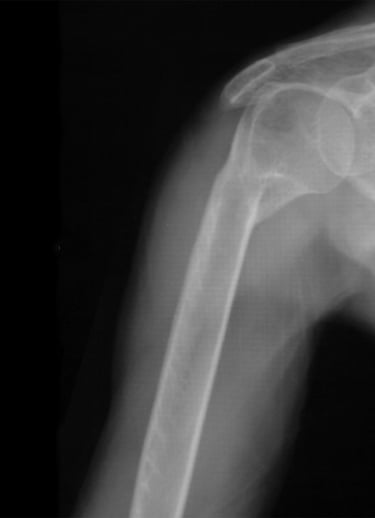

Gydytojas Markas Fiodorovas - ortopedas traumatologas, sporto traumų specialistas, sukaupęs 20 metų patirtį tausojančioje artroskopinėje chirurgijoje. Daugiau nei 650 artroskopinių kelio, peties ir kitų sąnarių operacijų per metus atliekantis chirurgas, taip pat aktyviai įsitraukęs į mokslinę veiklą. Gydytojas yra nuolatinis tarptautinių konferencijų lektorius bei tarptautinis artroskopinės chirurgijos instruktorius.